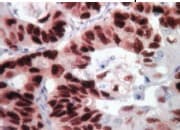

Mouse specific HRP/Dab Detection IHC Kit(ab64259)

Mouse specific HRP/Dab IHC Detection Kit ab64259 is a complete kit to detect a primary antibody raised in mouse, using HRP-labeled-streptavidin and a biotinylated anti-mouse secondary antibody.

Applications IHC-P